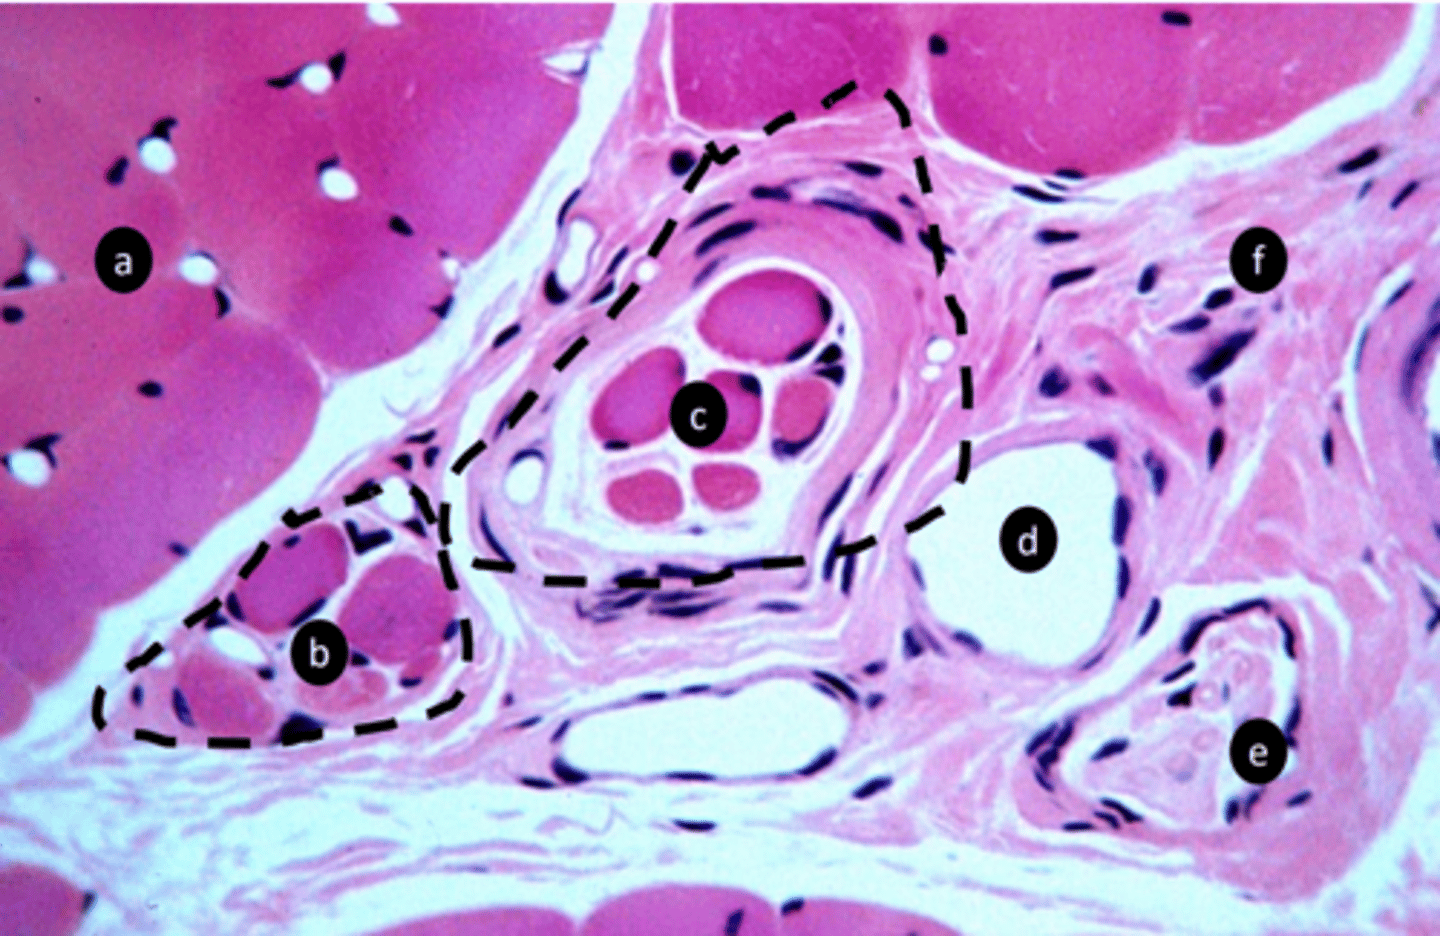

extrafusal myofibers

a: specific tissue type

intrafusal muscle fiber

b: specific tissue type

intrafusal muscle fiber (muscle spindle)

c: specific tissue type

stretch receptor, proprioception: detect length and velocity

function of c?

vein

e: structure

nerve fibers

f: structure